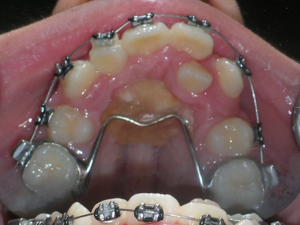

First Premolars were removed. We used an anchor device on the top jaw known as a “Nance” holding arch to help us retract the canines into the first premolar space. The holding device is used to reduce shifting of the top back teeth forward.